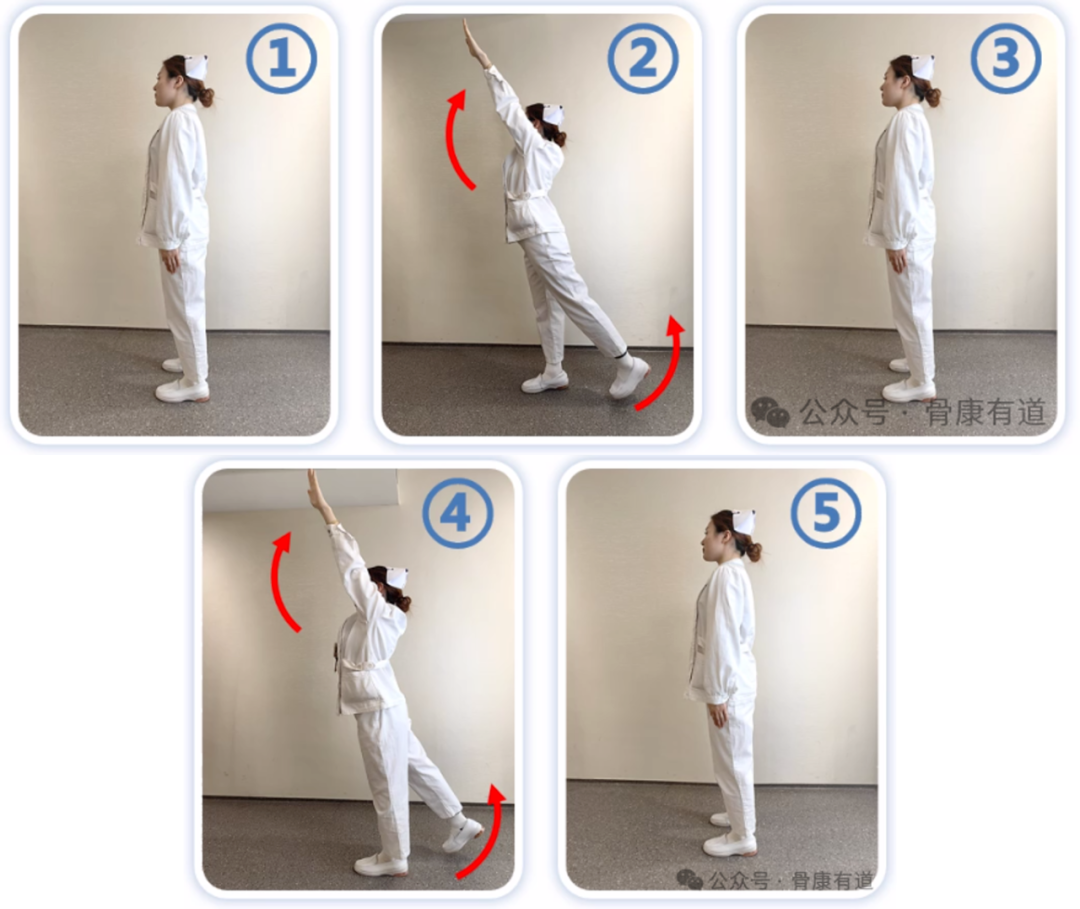

动作二:

①自然站立;

②左腿向后尽量抬起,同时两臂向上举起,稍作停顿;

③然后返回;

④换右腿向后尽量抬起,同时两臂向上举起;

⑤还原站立。

①-②-③-④-⑤为一组,左右交替10次。抬腿时膝盖尽量伸直,全程保持自然呼吸。